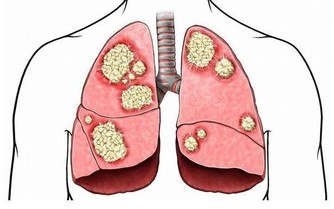

這些你不去注意,時間就了濕氣就會引發出一些大毛病比如:

如:高血壓、哮喘、脂肪肝、心腦血管等疾。